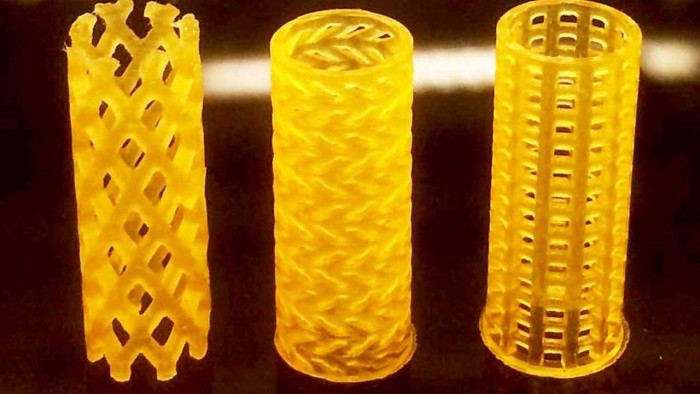

用于创建支架的3D打印过程被称为数字光处理,并使用专门为此目的调整的光敏树脂。该过程要求研究人员创建一个特定部分气道的计算机断层扫描图像,在将数据传输到DLP打印机之前,该图像用于开发支架的3D模型。

从打印机上照射的紫外光使树脂硬化,逐层构建支架。新建造出来的的树脂在室温下通常会太厚,需要在70至90摄氏度的温度下进行处理,然后需要一个特殊的工具来辅助安装,因为它们必须被折叠。植入物不能打结,也不能挤错方向,要精确地在目标位置展开。